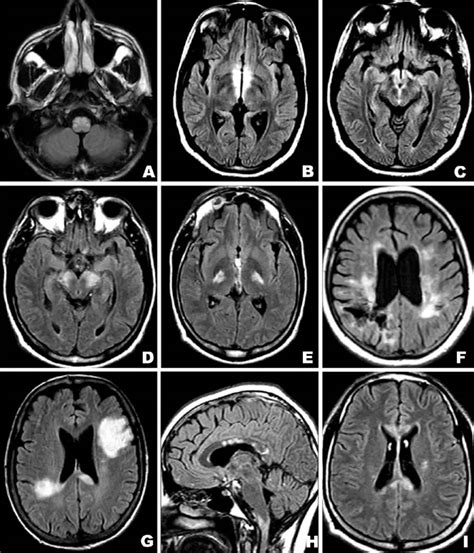

When considering diagnostic approaches, neuroimaging plays a pivotal role. Neuroimaging techniques are essential in diagnosing pseudoischemic lesions . Magnetic resonance imaging (MRI) is generally the preferred imaging modality due to its superior sensitivity and ability to detect subtle changes in brain tissue . MRI can provide detailed information about the location, size, and characteristics of the lesion, as well as identify any underlying abnormalities such as edema or inflammation. Diffusion-weighted imaging (DWI) is a specific MRI technique that is particularly useful in distinguishing between true ischemic lesions and pseudoischemic lesions . DWI measures the movement of water molecules in the brain tissue. In true ischemia, DWI typically shows a characteristic pattern of restricted diffusion, indicating a lack of blood flow. In contrast, pseudoischemic lesions may not show this pattern, or the pattern may be different, helping to differentiate them from true ischemia.

Computerized tomography (CT) scans can also be used in the evaluation of pseudoischemic lesions , although they are generally less sensitive than MRI. CT scans are particularly useful in the acute setting to rule out other potential causes of stroke-like symptoms, such as hemorrhage or mass lesions . However, CT scans may not be able to detect subtle changes associated with pseudoischemic lesions, particularly in the early stages. In addition to neuroimaging, other diagnostic tests may be necessary to determine the underlying cause of a pseudoischemic lesion . An electroencephalogram (EEG) can be used to assess for seizure activity, particularly in patients with a history of seizures or who present with symptoms suggestive of seizures. Blood tests may be performed to check for metabolic abnormalities, such as hypoglycemia or hyperglycemia, or to evaluate for inflammatory or infectious conditions. In some cases, a lumbar puncture may be necessary to analyze the cerebrospinal fluid (CSF) for signs of infection or inflammation . The diagnostic approach to pseudoischemic lesions should be individualized based on the patient’s clinical presentation, medical history, and risk factors. A thorough evaluation, including a detailed neurological examination, neuroimaging studies, and potentially other diagnostic tests, is essential to determine the underlying cause of the lesion and guide appropriate management. It’s like putting together a puzzle, where each piece of information helps to complete the picture.